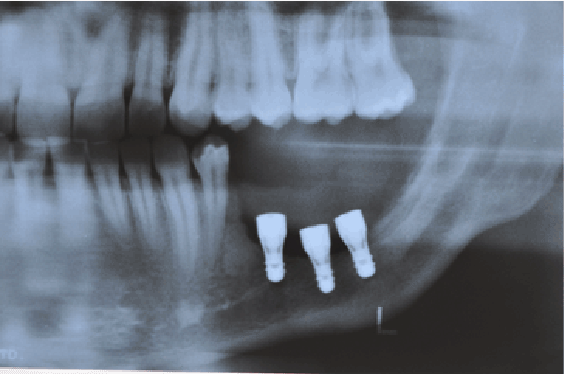

在移除造釉细胞瘤病变的手术后23个月,将3个种植体(RN标准加,瑞士Straumann - 4.1 mm/ 6mm)安装在剩余的骨中(图3)。种植体手术后5个月,安装金属陶瓷假体(图4)。使用x线照片和临床检查对患者进行监测,包括假体安装后24、36个月、造釉细胞瘤切除术后72个月(图5)。

图3:18个月随访-手术切除病灶后放置植入物。

图5:24个月后拍摄安装假体的x光片